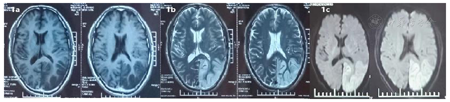

患者中年男性,反复卒中发作,伴有认知下降,外院以"病毒性脑炎"治疗效差,患者外院两次头颅磁共振提示左侧颞枕叶呈现类花边征样改变,且第二次磁共振(图2)提示病灶较第一次(图1)范围扩大,但前次磁共振病变在第二次磁共振呈现好转趋势,呈现"此消彼长"的特点,增强磁共振未病灶未强化(图3),头颈CTA未见异常(图4);患者发病来无四肢抽搐,根据病史及影像学定位为:大脑皮层、枕叶、左侧锥体束、左侧脊髓丘脑束,定性考虑:卒中?代谢性?炎性?感染?

患者入院前磁共振检查:

患者中年男性,反复卒中发作,伴有认知下降,外院以"病毒性脑炎"治疗效差,患者外院两次头颅磁共振提示左侧颞枕叶病变,第二次磁共振比第一次病灶面积增大,且磁共振提示病灶为分层样改变,患者发病来无四肢抽搐,根据病史及影像学定位为:大脑皮层、枕叶、左侧锥体束、左侧脊髓丘脑束,定性考虑:卒中?代谢性?炎性?感染?结合患者卒中样发作;影像学表现;认知障碍、血乳酸显著增高、磁共振波谱成像显示病灶、≥2次卒中样发作、患者母亲有糖尿病史、肌电图提示周围神经受累、体重下降、卒中样发作急性期病灶弥散加权成像(DWI)弥散受限,皮质受累尤为明显,呈现类花边征样改变。病灶具有进展性、可逆性、多发性以及呈现"此消彼长"的"游走性"特点[3,4]。